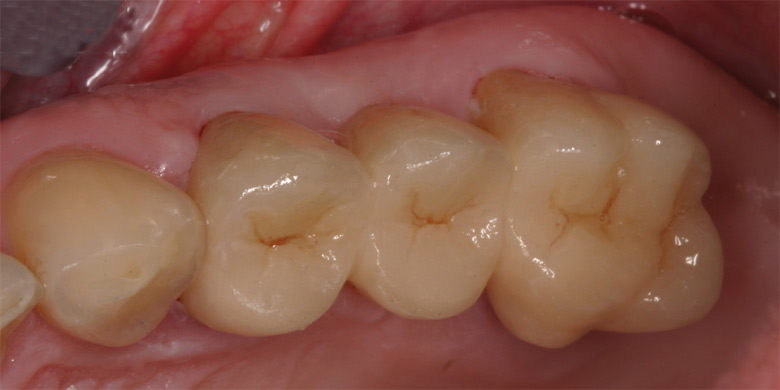

Particolare occlusale

del restauro.